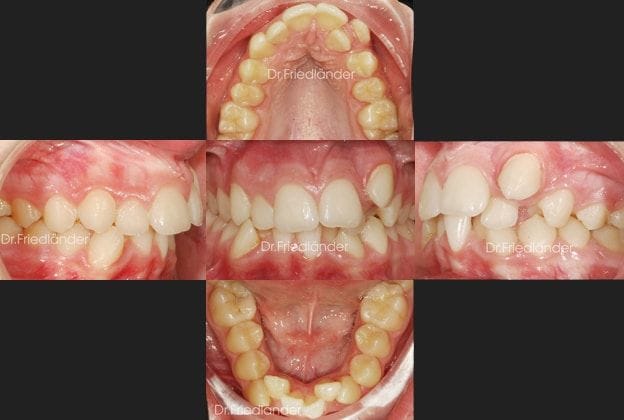

Caso 1 Tratamiento con brackets de autoligado y cuatro extracciones de premolares (Apiñamiento severo y encías delicadas)

En este caso no tuve más remedio que extraer 4 premolares en el tratamiento para poder hacer espacio a los demás dientes sin perjudicar la salud de las encías. Como se puede observar en las imágenes, la situación inicial es grave con respecto al apiñamiento y las encías tan delicadas.

Después del estudio de las radiografías, modelos y fotos que siempre hago, he llegado, junto con la paciente, a la decisión de que el mejor tratamiento de ortodoncia para su boca serían las 4 extracciones. (esta paciente fue tratada con brackets de autoligado y 4 microtornillos).

Vemos la situación inicial de la boca de la paciente y el apiñamiento y salud de sus encías:

Después de 20 meses de tratamiento con ortodoncia fija de autoligado.